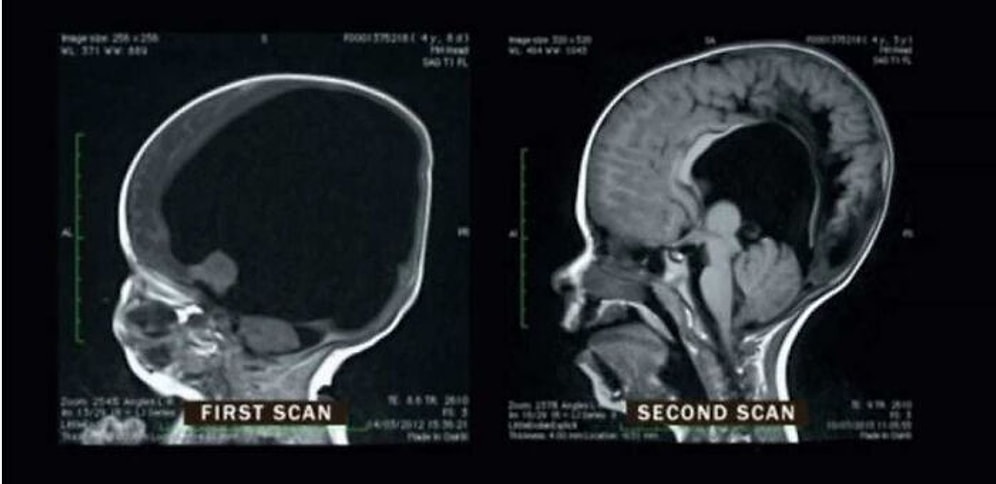

20 удивительных случаев из медицины, которые оставят вас с открытым ртом

Мир медицины удивителен. Например, только в прошлом году у 34-летнего мужчины появилась аллергия на холодный воздух. Был еще один бразильский парень, который удивил своих врачей тем, что у него было три почки. И это только верхушка айсберга. Есть масса памятных случаев, которые продолжают удивлять нас и по сей день. И вы можете найти большинство из них на сабреддите r / MEDizzy.